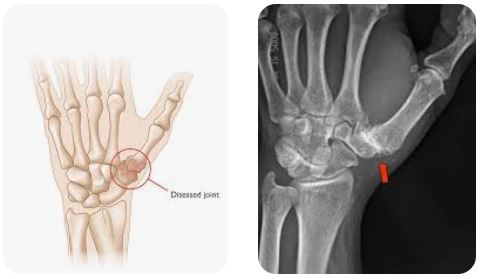

Thumb CMC arthritis is a common degenerative condition that causes pain, weakness, and reduced hand function, significantly impacting daily activities such as gripping, pinching, and fine motor tasks. When conservative treatments fail to provide adequate symptom relief, surgical intervention may be required. CMC arthroplasty is indicated to relieve pain, restore joint mechanics, and improve functional outcomes, allowing patients to regain hand strength, mobility, and quality of life.